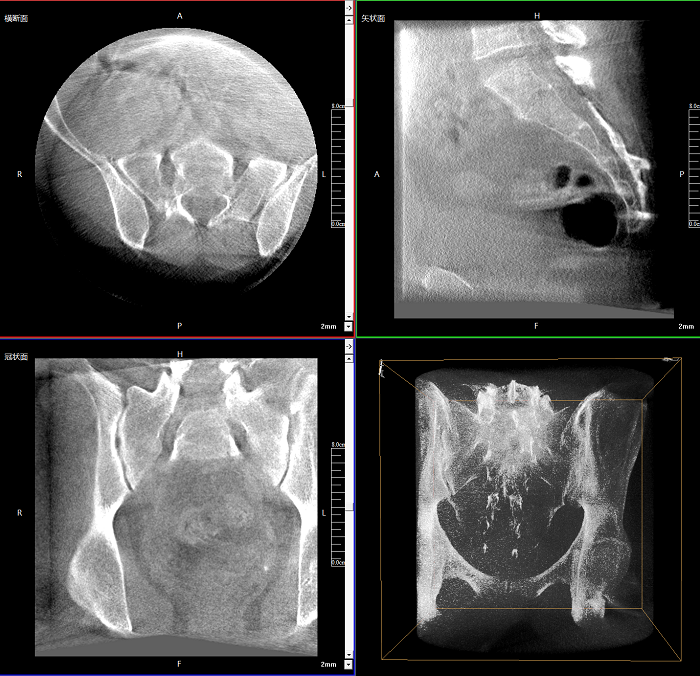

三維成像 全面觀察

任意視角、任意切面觀察

術中實時生成橫斷面、矢狀面、冠狀面及三維影像,可在任意切面、任意角度評估植入物和解剖結構的相對位置。

術中CT檢查 減少翻修概率

通過術中三維影像的檢查,可以立即發(fā)現(xiàn)植入物的錯位,減少不必要的第二次手術,減少并發(fā)癥概率以及感染風險。

Clinical picture

臨床圖片